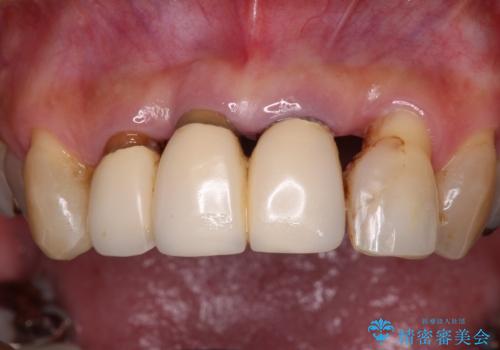

- 上顎前歯の違和感や不快感を気にして来院された患者様です。

現在のクラウンは金属の縁が見えており、歯と歯と歯肉の間に大きなスペースができていて、見た目も悪く、物が挟まったり話しにくかったりしていました。

また、前歯に抜歯が必要な歯があったため、抜歯をし、傷の治りを待ってオールセラミックブリッジにて補綴治療を行うこととしました。